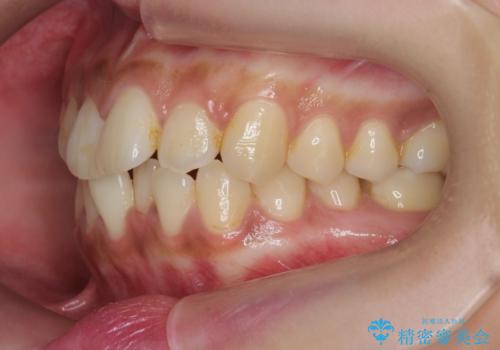

前歯のがたつきをすっきり マウスピース矯正

- 長年気になっていた前歯のがたつきをマウスピース矯正で治したい!と希望され来院されました。

奥歯の噛み合わせには問題がなく、前歯のがたつきの改善のみで十分に審美的な結果が得られるため、ワイヤーではなくマウスピース矯正での治療を計画します。

しっかりと前歯のがたつきは改善し見た目が大きく良くすることができました。